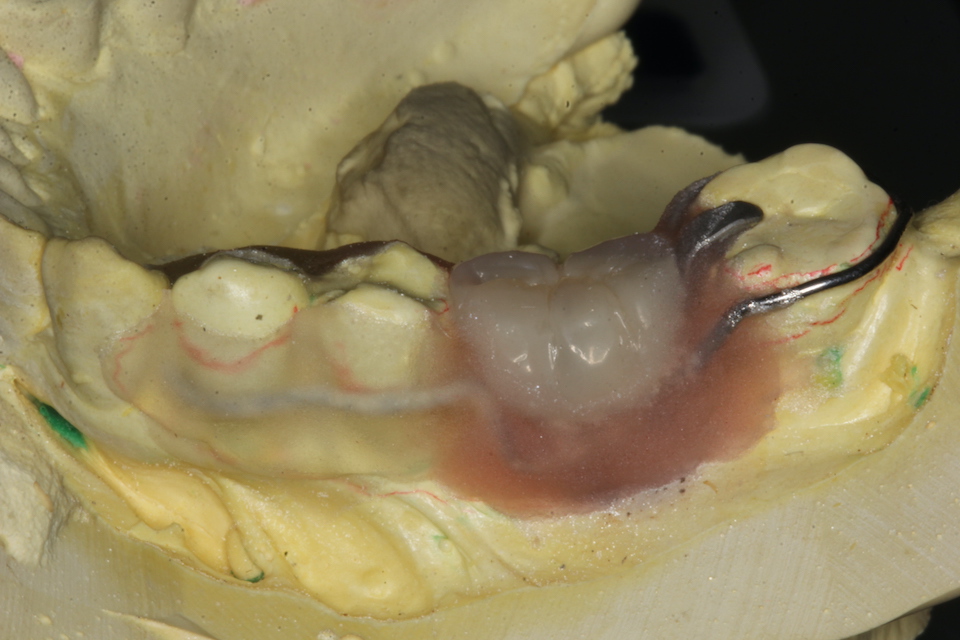

半口腔内製作義歯0.3

70代男性、上顎義歯前回のつづきhttps://plaza.rakuten.co.jp/mabo400dc/diary/202505260001/3回の来院で終わることができる義歯の作り方です。少子高齢化で人手不足と患者激増に対処するために非常に低コストで究極の省力化を目指した義歯の製作方法です。3回というのは歯科医師側から見ると普通なのですが、歯科医師は間に入る技工作業をすることはなく外注するわけですが、それは診療室の作業と比べると10倍程の作業量があるわけで、それも含めた省力化ということなのです。フレームは半円線とφ0.8mmのクラスプ線を作業模型上で曲げて蝋着してつくる。見えるところは金属のオペーク色を塗布する。作業模型上で矯正用のレジンの筆積み法で床を作る。クラスプはノンクラスプの設計だが、即時重合レジンの場合は補強線は必要。口腔内で直接レジンでバイトを採れるように突起を作る。バイトを取ったら咬合器装着して、ハイブリッドレジンで人工歯作成。既成の人工歯を削って作るのは時間がかかり過ぎる。ハイブリッドレジンは高価なのでなるべく薄くなるように内部は透明レジンで作る。次回は口腔内セット予定。